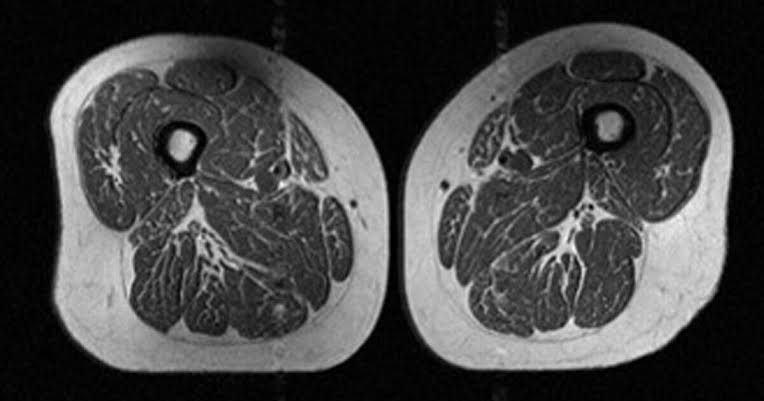

X-ray photographs of a woman's thigh published in a newly released study show how ultra-processed fo...

X-ray photographs of a woman's thigh published in a newly released study show how ultra-processed foods negatively impact the body.